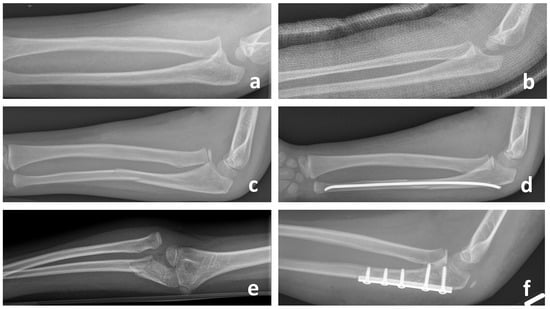

A treatment option for chronic Monteggia injuries under the age of 10 years is a percutaneous subtotal osteotomy of the ulna with closed reduction of the radial head using a miniaturized external fixator (Figure 4a–d) [28,29]. After determining the osteotomy site, two fixator clamps are placed percutaneously proximally and distally under fluoroscopic control and the percutaneous osteotomy of the proximal third of the ulna is performed via an approx. 1 to 2 cm long approach. We recommend an osteotomy of the proximal ulna at least 1 cm distal to the coronoid process, which reinforces the downward pull of the interosseous membrane. This maximizes tension on the interosseous membrane, which contributes to the reduction of the radial head and prevents subluxation or re-dislocation [5,17,22]. In addition, an osteotomy chosen as proximally as possible improves the advantage of a larger bone contact surface, which results in faster and better bone healing and eliminates the need for bone grafting. In children of this age, excellent bone healing typically obviates the need for additional bone grafting. However, it is better to preserve the far cortex of the osteotomy for better and faster healing of the osteotomy gap (Figure 4b–d,f–h). According to the literature, if a wedge gap of more than 1 cm remains at the osteotomy site, a primary bone graft from the iliac crest [30] or an osteoconductive bone graft substitute [31] can be used to prevent nonunion. However, if such a large osteotomy gap occurs, a lengthening of the ulna is more likely to be indicated.

An alternative to proximal ulnar osteotomy is CORA-based osteotomy (Figure 4a). However, it is often difficult to determine the center of rotation and angulation due to the long-standing injury. While some authors theorize that an osteotomy at the CORA restores a normal width of the interosseous membrane and at the same time eliminates the anteriorly bent deformation of the ulna, they believe this is an obstacle for radial head repositioning. Several studies report an increased risk of radial head dislocation and reduced forearm rotation in osteotomies at the CORA, which is why a proximal ulnar osteotomy is preferred in the literature [20,31,32]. After osteotomy of the ulna, the closed reduction of the radial head is enabled by angulation, flexion and lengthening of the ulna. If an anatomical reduction of the radial head is not possible, an open reduction with a resection of the scar tissue is performed via the Kocher approach [28,33]. The fixator remains in place for 6–12 weeks and can be removed on an outpatient basis without anesthetic.

4.1.2. Ulnar Osteotomy and Correction with Plate Osteosynthesis

In older children and adolescents and in cases where the use of an external fixator is not an option due to lack of compliance or if the patient and/or parents do not prefer, a corrective proximal ulnar osteotomy and stable plate osteosynthesis is recommended. A subtotal dorsal osteotomy of the proximal third of the ulna is performed by an extended Kocher approach through an additional dorsal window in the anconeus muscle, whereby the length and angulation of the ulna is adjusted under radiological control until a reduction of the radial head is achieved. Another osteotomy option for the lengthening of the ulna without bending is a Z-shaped stepped incision osteotomy [34]. However, a lower dislocation recurrence rate and better functional outcome can be achieved with angulation through the lengthening of the ulna in the direction opposite to the dislocation of the radial head [17,22]. In most cases, open reduction of the radial head is required as the remnants of the original ligament and scar tissue impacts into the joint. After reduction of the radial head and temporary fixation with a monolateral external fixator, a pre-bent plate osteosynthesis is used (Figure 5a–e) [35]. Instead of an external fixator, K-wire fixation through the capitellum into the radial head may be used temporarily to maintain the reduction of the radial head. In rare cases with an irreducible radial head, an additional corrective osteotomy of the proximal radius may be required [36]. In these complex cases, computer-aided 3D planning with RPT technology is recommended [37,38]. This procedure can also be used to correct an existing valgus or varus deformity by flexing the ulna. The authors recommend immobilization in a plaster cast 2 weeks after surgery, followed by a motion orthosis (ROM: Ex/Flex: 0–20–120°) for a further 4 weeks. Hardware removal is recommended after 6–12 months, depending on bone consolidation.

Figure 4. This figure shows the treatment course for the reconstruction of two missed Monteggia fractures in 9-year-old children. Panels (ad) depict an angulating proximal ulnar osteotomy with an external fixator and closed reduction of the radial head. This approach was undertaken after a failed external osteotomy at the CORA using plate osteosynthesis. Panels (eh) illustrate an angulating proximal ulnar osteotomy with plate osteosynthesis combined with an open reduction of the radial head. In both cases, the far cortex of the osteotomy was left intact to promote faster and improved healing without bone grafting. Radiographs at 4 weeks (c,g) already demonstrate evidence of consolidation, with complete healing observed at 3 months (d,h) and no signs of nonunion.